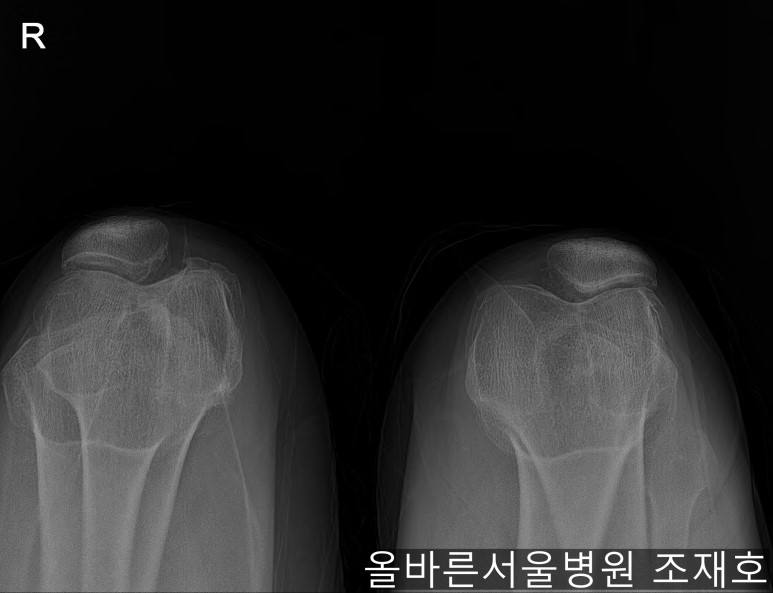

某患者,女,54岁,大面积软骨损伤,伴随内翻畸形,实施非切开CARTSTIEM手术及胫骨近端外翻截骨术,2、3年前右侧膝盖开始疼痛,在其他医院做了两次关节镜手术后疼痛加剧,膝关节变形严重遂到本院接受治疗。

仅通过放射线片子观察到:右膝由于炎症严重,内侧胫骨及股骨已接触在一起,向内测严重变形。

膝虽然也观察到了炎症,但远不如右膝严重。

如果通过X光片也观察到相同的病症,可以判断内侧关节的软骨大部分都损伤了。